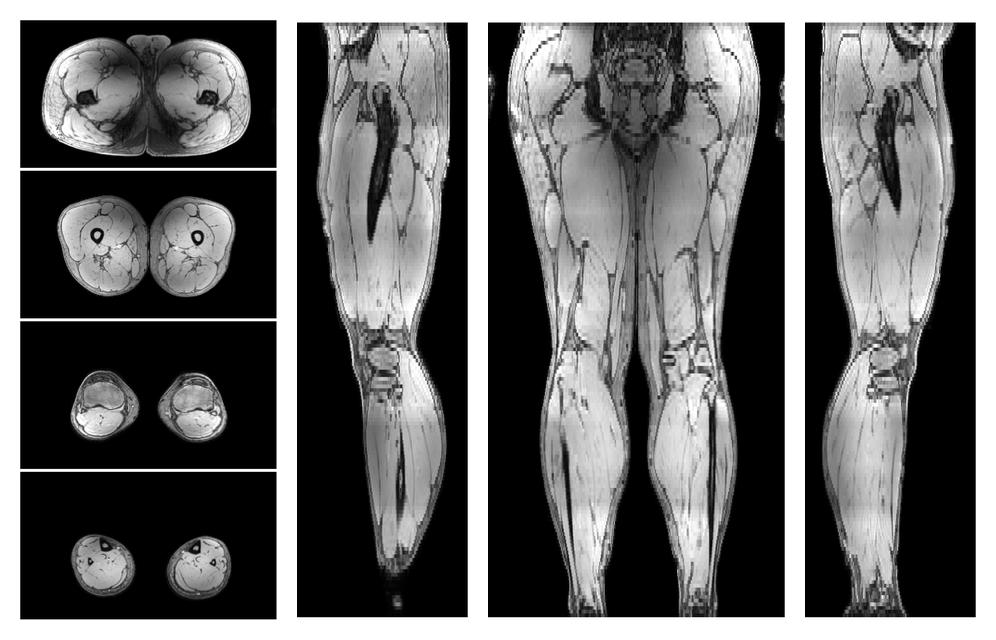

• Water only signal

The water part of the acquired multi-echo spin echo data.

• Water only T2 relaxation time

The water only T2 relaxation time of the lower extremity obtained from multi echo spin echo t2 mapping with EPG based reconstruction.